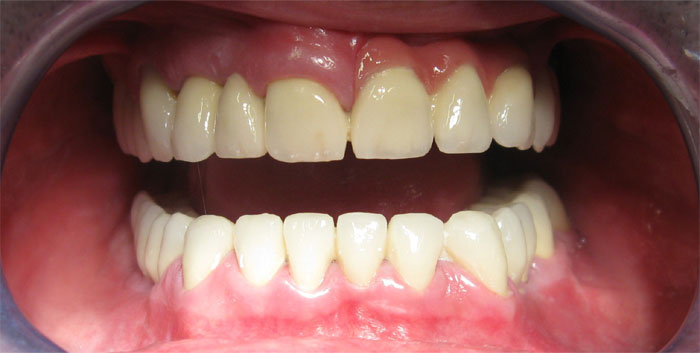

Nachfolgend finden Sie Fotos und Interview-Videos von Patienten, die in der Klinik Europa Dental implantatgetragene Brücken haben machen lassen.

Fall Nr. 1: Brücke auf Alpha-Bio-Implantaten und Brücke auf natürlichen Zähnen